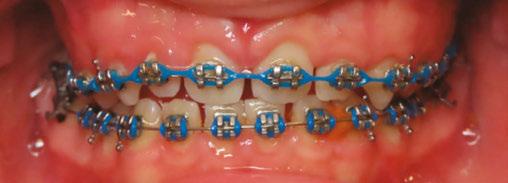

The history of myofunctional therapy in conjunction with orthodontic treatment dates to as early as 1906 with the publication of American orthodontist Alfred Rodgers’ “Living Orthodontic Appliance.” Rodgers presumed that muscle alone would correct a malocclusion.1 To further this claim, Edward Angle theorized that “every malocclusion has a myofunctional cause.”2 Angle’s contribution to myofunctional therapy relied primarily on fixed orthodontic appliances (Figure 1). However, the myofunctional component of orthodontics with fixed appliances fell out of favor when relapse occurred in a high percentage of patients coupled with time-consuming techniques to achieve results. Hence, tooth-centered orthodontics with extractions or self-ligating brackets without the need for extractions grew in popularity (Figure 2). Nevertheless, post-orthodontic relapse was still problematic, requiring permanent retainers. As George Hahn once wrote in his publication “Retention — The Stepchild of Orthodontia,” Irrespective of the length of time a tooth is held in its new position … upon release, it will seek a place where it is in balance.”3 Myofunctional therapy has made significant strides in using specifically designed exercises to bring oral, facial, and